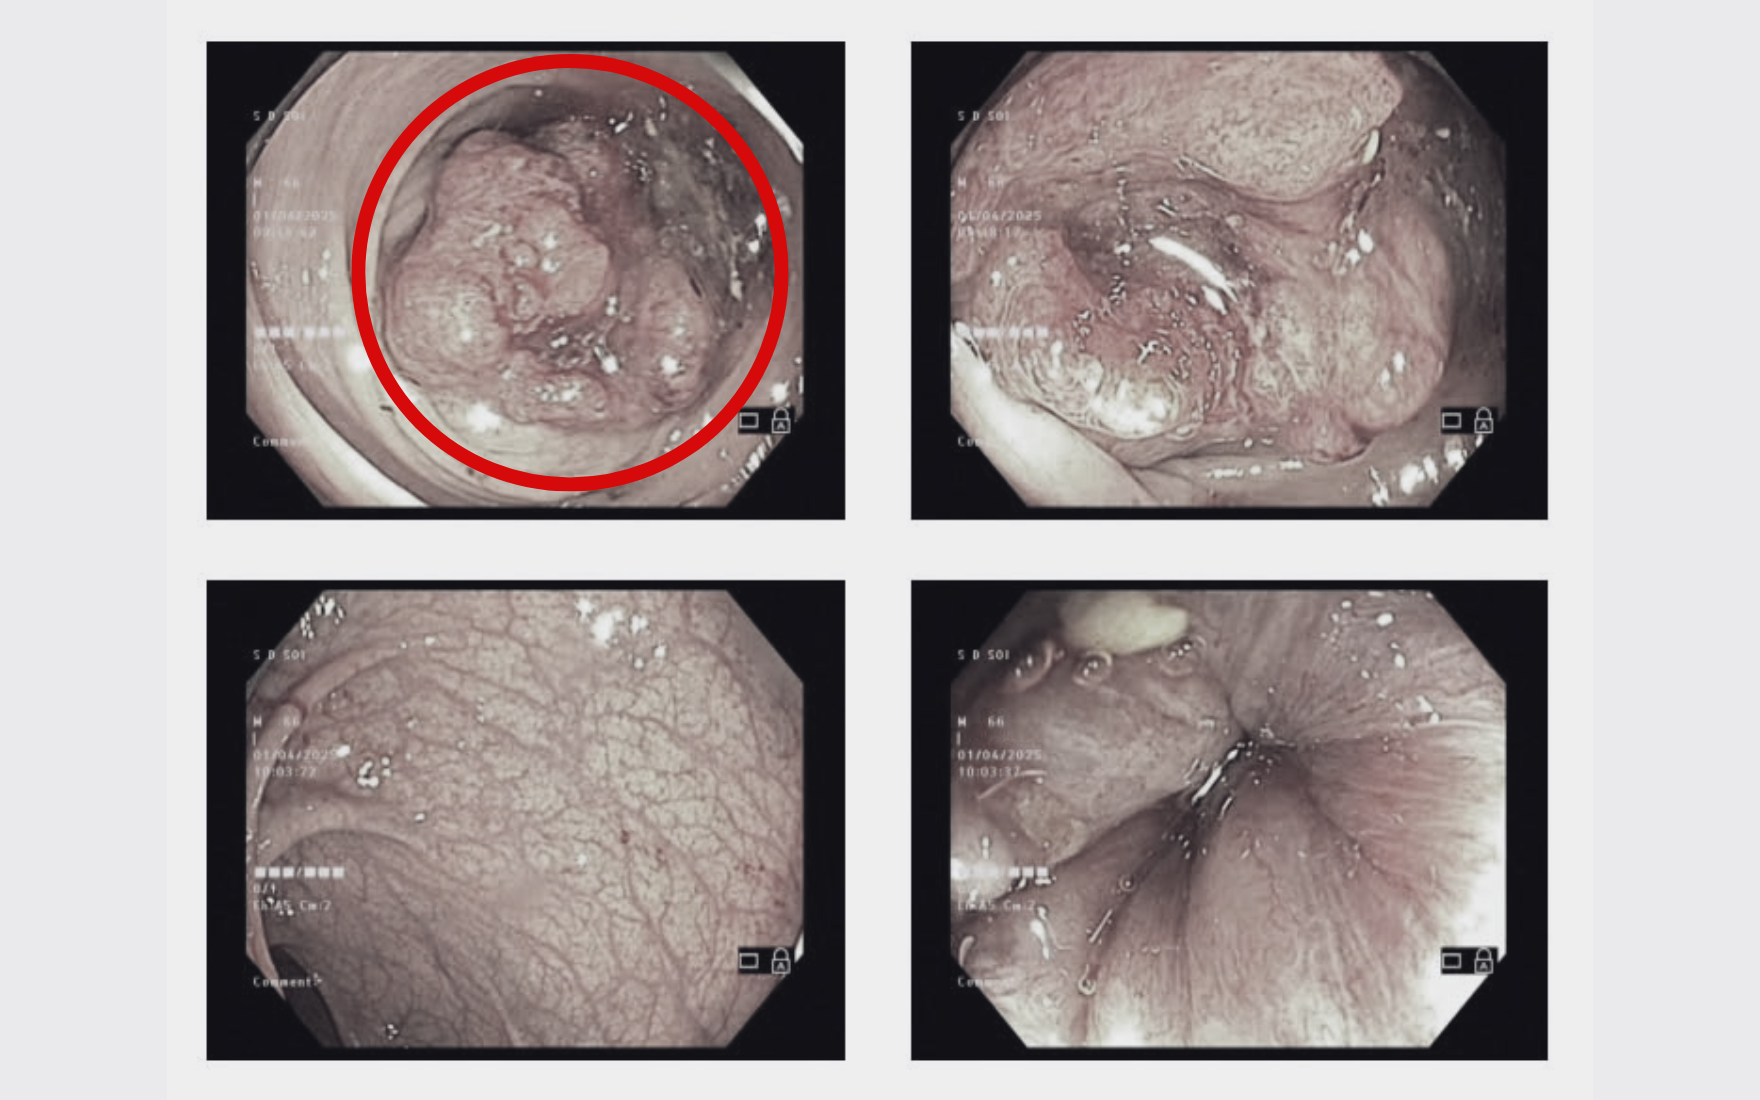

Trong quá trình nội soi đại tràng cho bệnh nhân, bác sĩ phát hiện cách rìa hậu môn 19cm của bệnh nhân S có khối sùi, mủn loét nham nhở, kích thước lớn 5cm, chân rất rộng. Ngay lập tức, ê kip lấy mẫu 6 mảnh tổn thương sinh thiết, xác định bệnh nhân mắc ung thư biểu mô tuyến biệt hóa vừa.

"Khối u kích thước lớn, lấp kín khẩu kính đại tràng, có dấu hiệu sùi loét và đã phát triển thành ung thư. Tuy nhiên, bệnh nhân được phát hiện ở giai đoạn này là vẫn may mắn, chỉ cần 1 - 2 tháng nữa, khối u có thể xâm lấn sâu hơn hoặc di căn thì việc điều trị phức tạp hơn rất nhiều, thậm chí không thể phẫu thuật triệt căn" - ThS.BS Cù Trung Kiên, Phó khoa Ngoại tiêu hóa - BVĐK Hồng Ngọc Yên Ninh, bác sĩ trực tiếp điều trị cho bệnh nhân S cho biết.

Khối u sùi lấp kín lòng đại tràng của bệnh nhân S